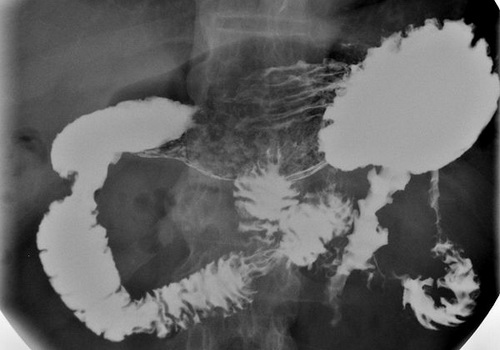

Symptoms differ according to the actual site of the cancer. Cancer located at the head of the pancreas will obstruct the common bile duct and cause jaundice, itching, early satiety, sticky oily stools and dark urine. Cancers in the tail of the pancreas will irritate the parietal peritoneum and cause chest pain or upper abdominal pain. These features associated with dramatic weight loss, past history of pancreatitis or family history places pancreatic cancer high up on the list of differential diagnoses. Liver function tests (AST, ALT and ALP) and conjugated bilirubin levels may be elevated. Carbohydrate antigen 19-9 (CA 19-9) levels are frequently elevated in patients with pancreatic cancer. An ultrasound of the abdomen may detect a mass in the pancreas and a dilation of extra hepatic bile ducts suggesting an obstruction and free fluid in the abdomen (ascites). Computer tomography also can be used to demarcate the lesions. Endoscopy guided biopsy will give a definitive diagnosis.